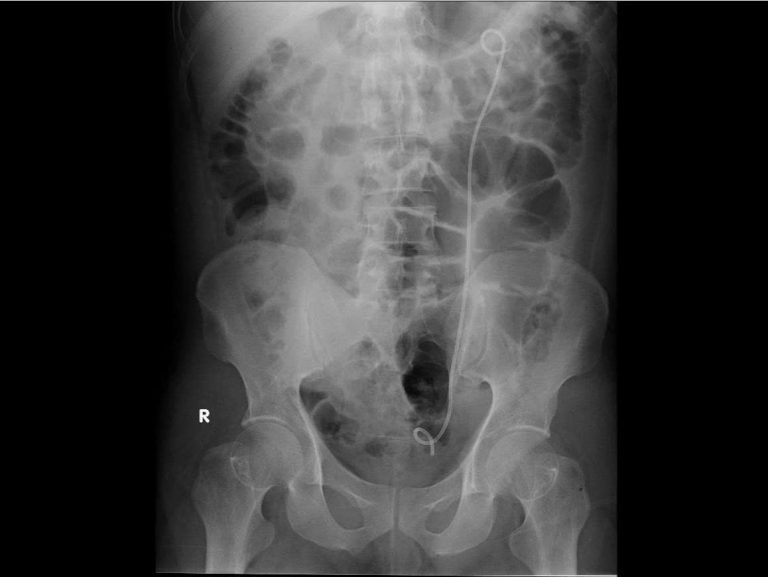

Hình ảnh phim CT trước mổ cho thấy thận có sỏi niệu quản bị ứ nước - Ảnh BVCC

Kết quả CT-scan bụng cho thấy có một viên sỏi nằm ở niệu quản trái đoạn lưng, gây tắc nghẽn hoàn toàn đường thoát nước tiểu - đây chính là thủ phạm khiến thận trái bị ứ và nhiễm trùng.

Các xét nghiệm máu, nước tiểu và hình ảnh học cho thấy chỉ số nhiễm trùng tăng cao, có dấu hiệu thận trái đã bị ứ mủ và chức năng của thận bị suy giảm.